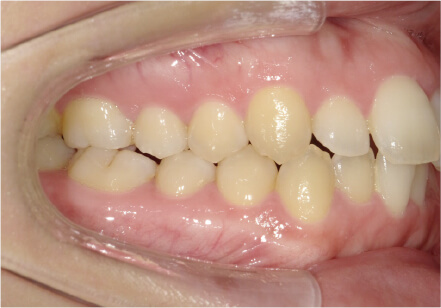

叢生の症例

19歳

/

女性

相談内容

上の前歯が出っ歯、下の前歯がガタガタ

カウンセリング・診断結果

抜歯承諾、IPR承諾、アタッチメント承諾、ミニインプラント承諾、アレルギー有・叢生(凸凹)

治療内容・方法

全顎アライナー矯正 抜歯予定だったが抜歯リスク高いため抜歯なしでIPR量を増やす

術後の経過・現在の様子

クリアライナー

治療のリスク

痛み・歯根吸収・歯肉退縮・虫歯・後戻り

費用・治療期間

880,000円、1年5ヶ月

トレーニングなど